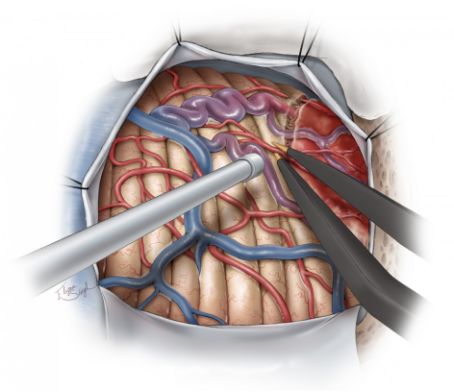

以下示意图体现了切除右侧小脑囊性HB的原则,同样适用于其他部位相同类型的囊性HB。

图5. 硬膜内暴露并辨认壁结节,壁结节可能突出脑皮层抑或者位于浅表脑皮层处,笔者们可以观察到软脑膜表面颜色明显不同,有明显的供血动脉及引流静脉。如果壁结节位于深部且囊壁塌陷,则寻找起来有一定困难。如果壁结节位于囊腔的深部,而不是囊腔表面,则脑皮层表面没有明显的颜色变化,无法与周围正常的脑组织区分,给术中定位增加不少难度。壁结节的供血动脉及引流静脉清楚地勾勒出类似AVM的血管结构(上图)。血管荧光造影更能显示肿瘤血管的走向,壁结节呈均匀高亮(右下图)。

图6. 肿瘤结节边界、供血动脉及引流静脉可以通过脑皮层表面的颜色变化来辨认,双极电凝经常用来分离结节与供血动脉。术者切记不能直接打开壁结节,需要应用切除AVM的显微手术原则进行操作。如果术中不慎打开了壁结节,可用一块止血棉片进行压迫止血,其次也可以选择双极电凝进行止血。术者应沿病变周边环形离断供血动脉,并保持所有可能呈动脉化的静脉。

如果供血动脉对结节的血供并不丰富,术者就可以较为容易地控制结节内的血流,并像切除肿瘤一样将其切除。然而,离断主要供血动脉时仍需谨慎操作。

图7. 一旦肿瘤的供血动脉离断后,可以开始离断引流静脉,并沿脑白质与结节之间的胶样化带进行分离。AVM有来自深部脑白质的供血动脉,但HB没有,这极大简化了手术过程,最终,整块切除结节。

图8. 囊壁并不要求全部切除,当切除结节后,探查囊壁,确认结节是否全部切除,随后进行彻底止血。